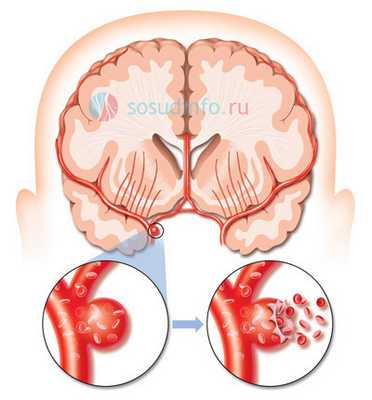

Аневризма сосудов головного мозга - это серьезное заболевание, при котором в стенке артерий головного мозга образуется локальное выпячивание, обусловленное истончением и потерей эластичности пораженного участка стенки. Как показывает статистика, с данной патологией сталкивается около 5% населения. При отсутствии лечения она может осложняться таким жизнеугрожающим состоянием, как разрыв аневризмы. Основным методом лечения этой болезни является хирургическое вмешательство. В данное статье мы поговорим о такой оперативной технике, как клипирование аневризмы сосудов головного мозга.

Из клинических проявлений аневризмы головного мозга можно отметить как незначительные признаки (головные боли, тошнота, общая слабость, нечеткость и помутнение зрения), так и яркую симптоматику, обусловленную не только значительными размерами аневризмы, но и спонтанным ее разрывом с возникновением кровоизлияния в мозг. Опасность аневризмы в том, что человек с ее разрывом и кровоизлиянием может просто мгновенно погибнуть или остаться глубоким инвалидом. Поэтому при диагностированной аневризме сосудов головного мозга принимается решение о ее клипировании или эмболизации.